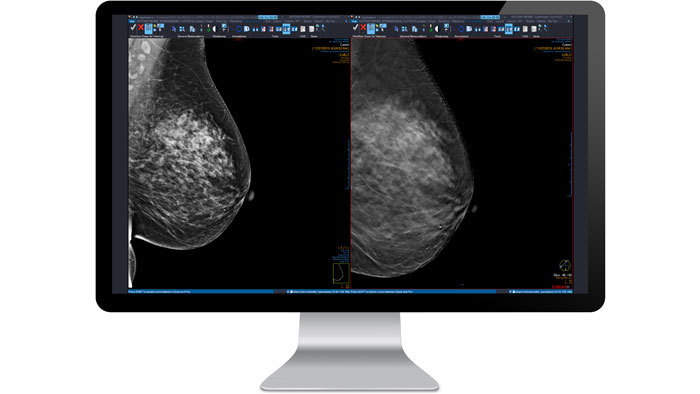

Mammography

Read traditional mammograms, breast ultrasound, breast MRI, digital breast tomosynthesis (DBT) and general radiography exams all from a single desktop. Automatic positioning and same-sizing allows easy image comparison of prior exams and multiple modalities with no manual manipulation required.

Simple

View multi-modality, multi-vendor images in a single desktop, including mammographs, DBT, general radiology exams and non-DICOM data.

Optimized

Decrease reading time and fatigue with industry-leading diagnostic tools, user-configurable protocols and automatic positioning and sizing for comparison of multiple modalities and priors.

Powerful

Improve diagnostic confidence with DBT support, computer-aided detection, cross-reference lines between suspicious areas on multiple views, and alerts for unread images.

Multi-modality support

The mammography module supports multi-modality, multi-vendor PACS, with consolidated image access on a single workstation. Screen and diagnose with confidence with our user-configurable intelligent display protocols for automated workflow, industry-leading mammography toolset, computer-aided detection (CAD) and optimized comparison of multiple priors.

Digital breast tomosynthesis (DBT)

Streamline workflows, optimize comparisons, and enhance diagnostic confidence with a complete set of integrated tools for low-dose 3D mammography. The DBT module for Vue Mammo adds unique workflow capabilities and specialized tools that optimize the reading of digital breast tomosynthesis exams at the same time as other procedures.

Whole breast ultrasound (ABUS)

As part of the Philips Clinical Collaboration Platform, the Breast Imaging Module offers a versatile solution that allows physicians to read digital Mammograms, Breast Ultrasound, Automated Breast Ultrasound (ABUS), General Radiology or Digital Breast Tomosynthesis (DBT) exams from a single desktop.